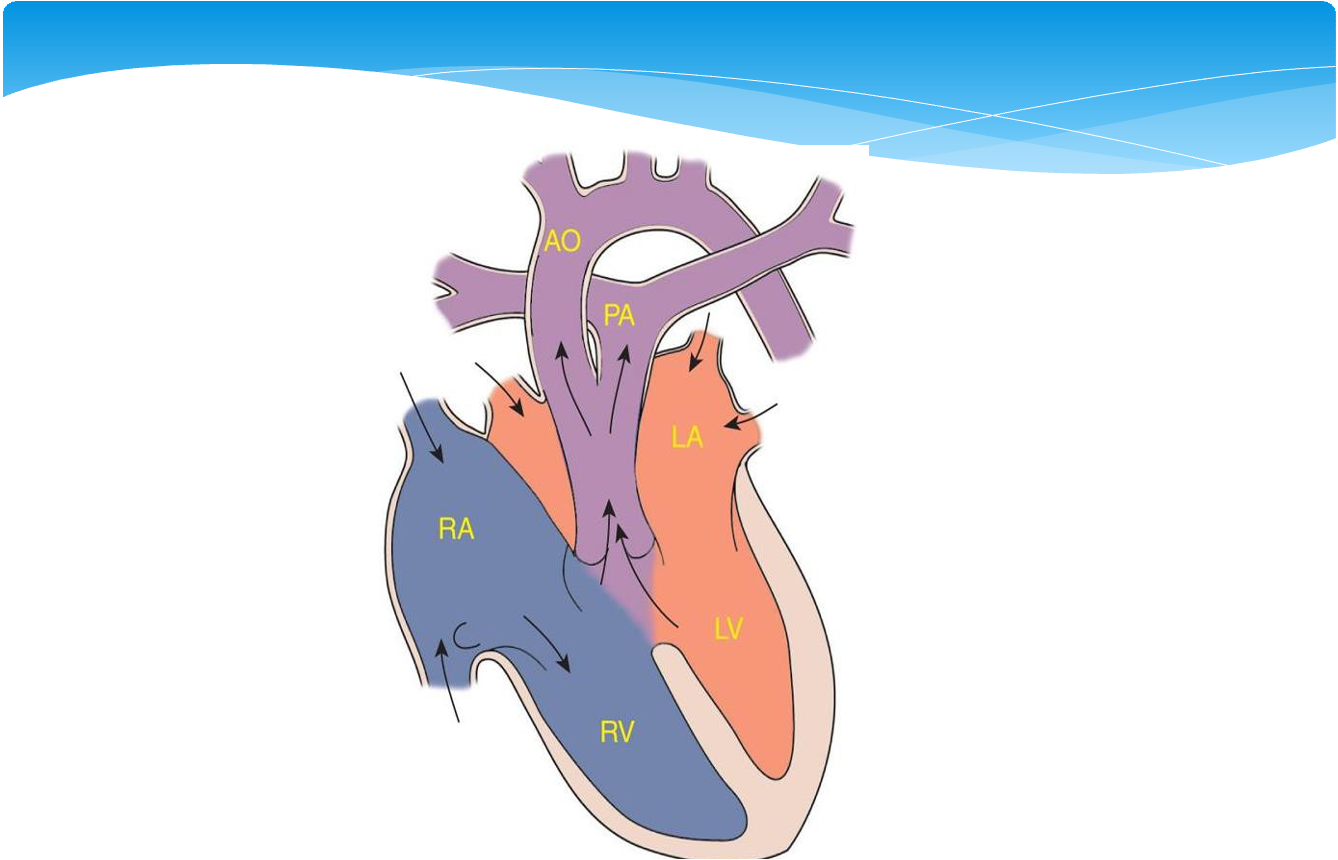

- Transposition of the Great Arteries

- Total Anomalous Pulmonary Venous Drainage

- Truncus Arteriosus

- Hypoplastic Left Heart Syndrome

Transposition of the Great Arteries

- Although dextroposed transposition of the great arteries represents only about 5% of congenital heart defects, it is the most common cyanotic lesion to present in the newborn period.

- A history of cyanosis is always present, although it depends on the amount of mixing. Tachypnea and a single S2 are typically present. If the ventricular septum is intact, there may be no murmur.

- Children with transposition and a large VSD have improved intracardiac mixing and less cyanosis. They may present with signs of heart failure. The heart is hyperdynamic, with palpable left and right ventricular impulses. A loud VSD murmur is heard. S2 is single.